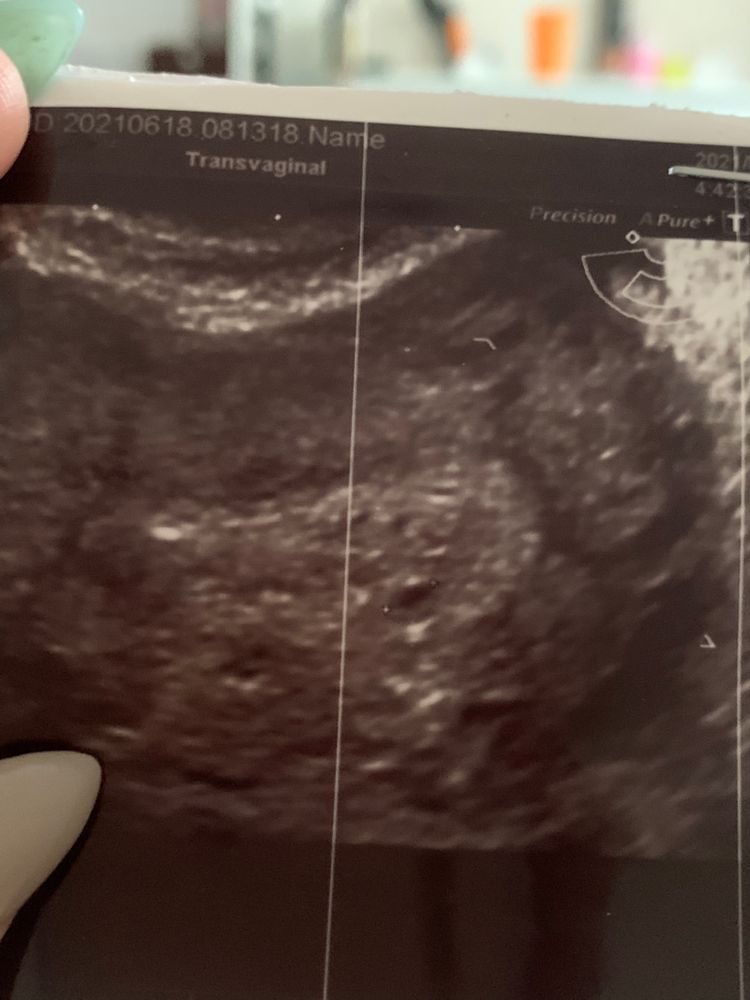

Сходила вчера на узи,срок 4 недели и 3 дня по месячным😃 Маленькая бусинка в матке уже❤️🐣